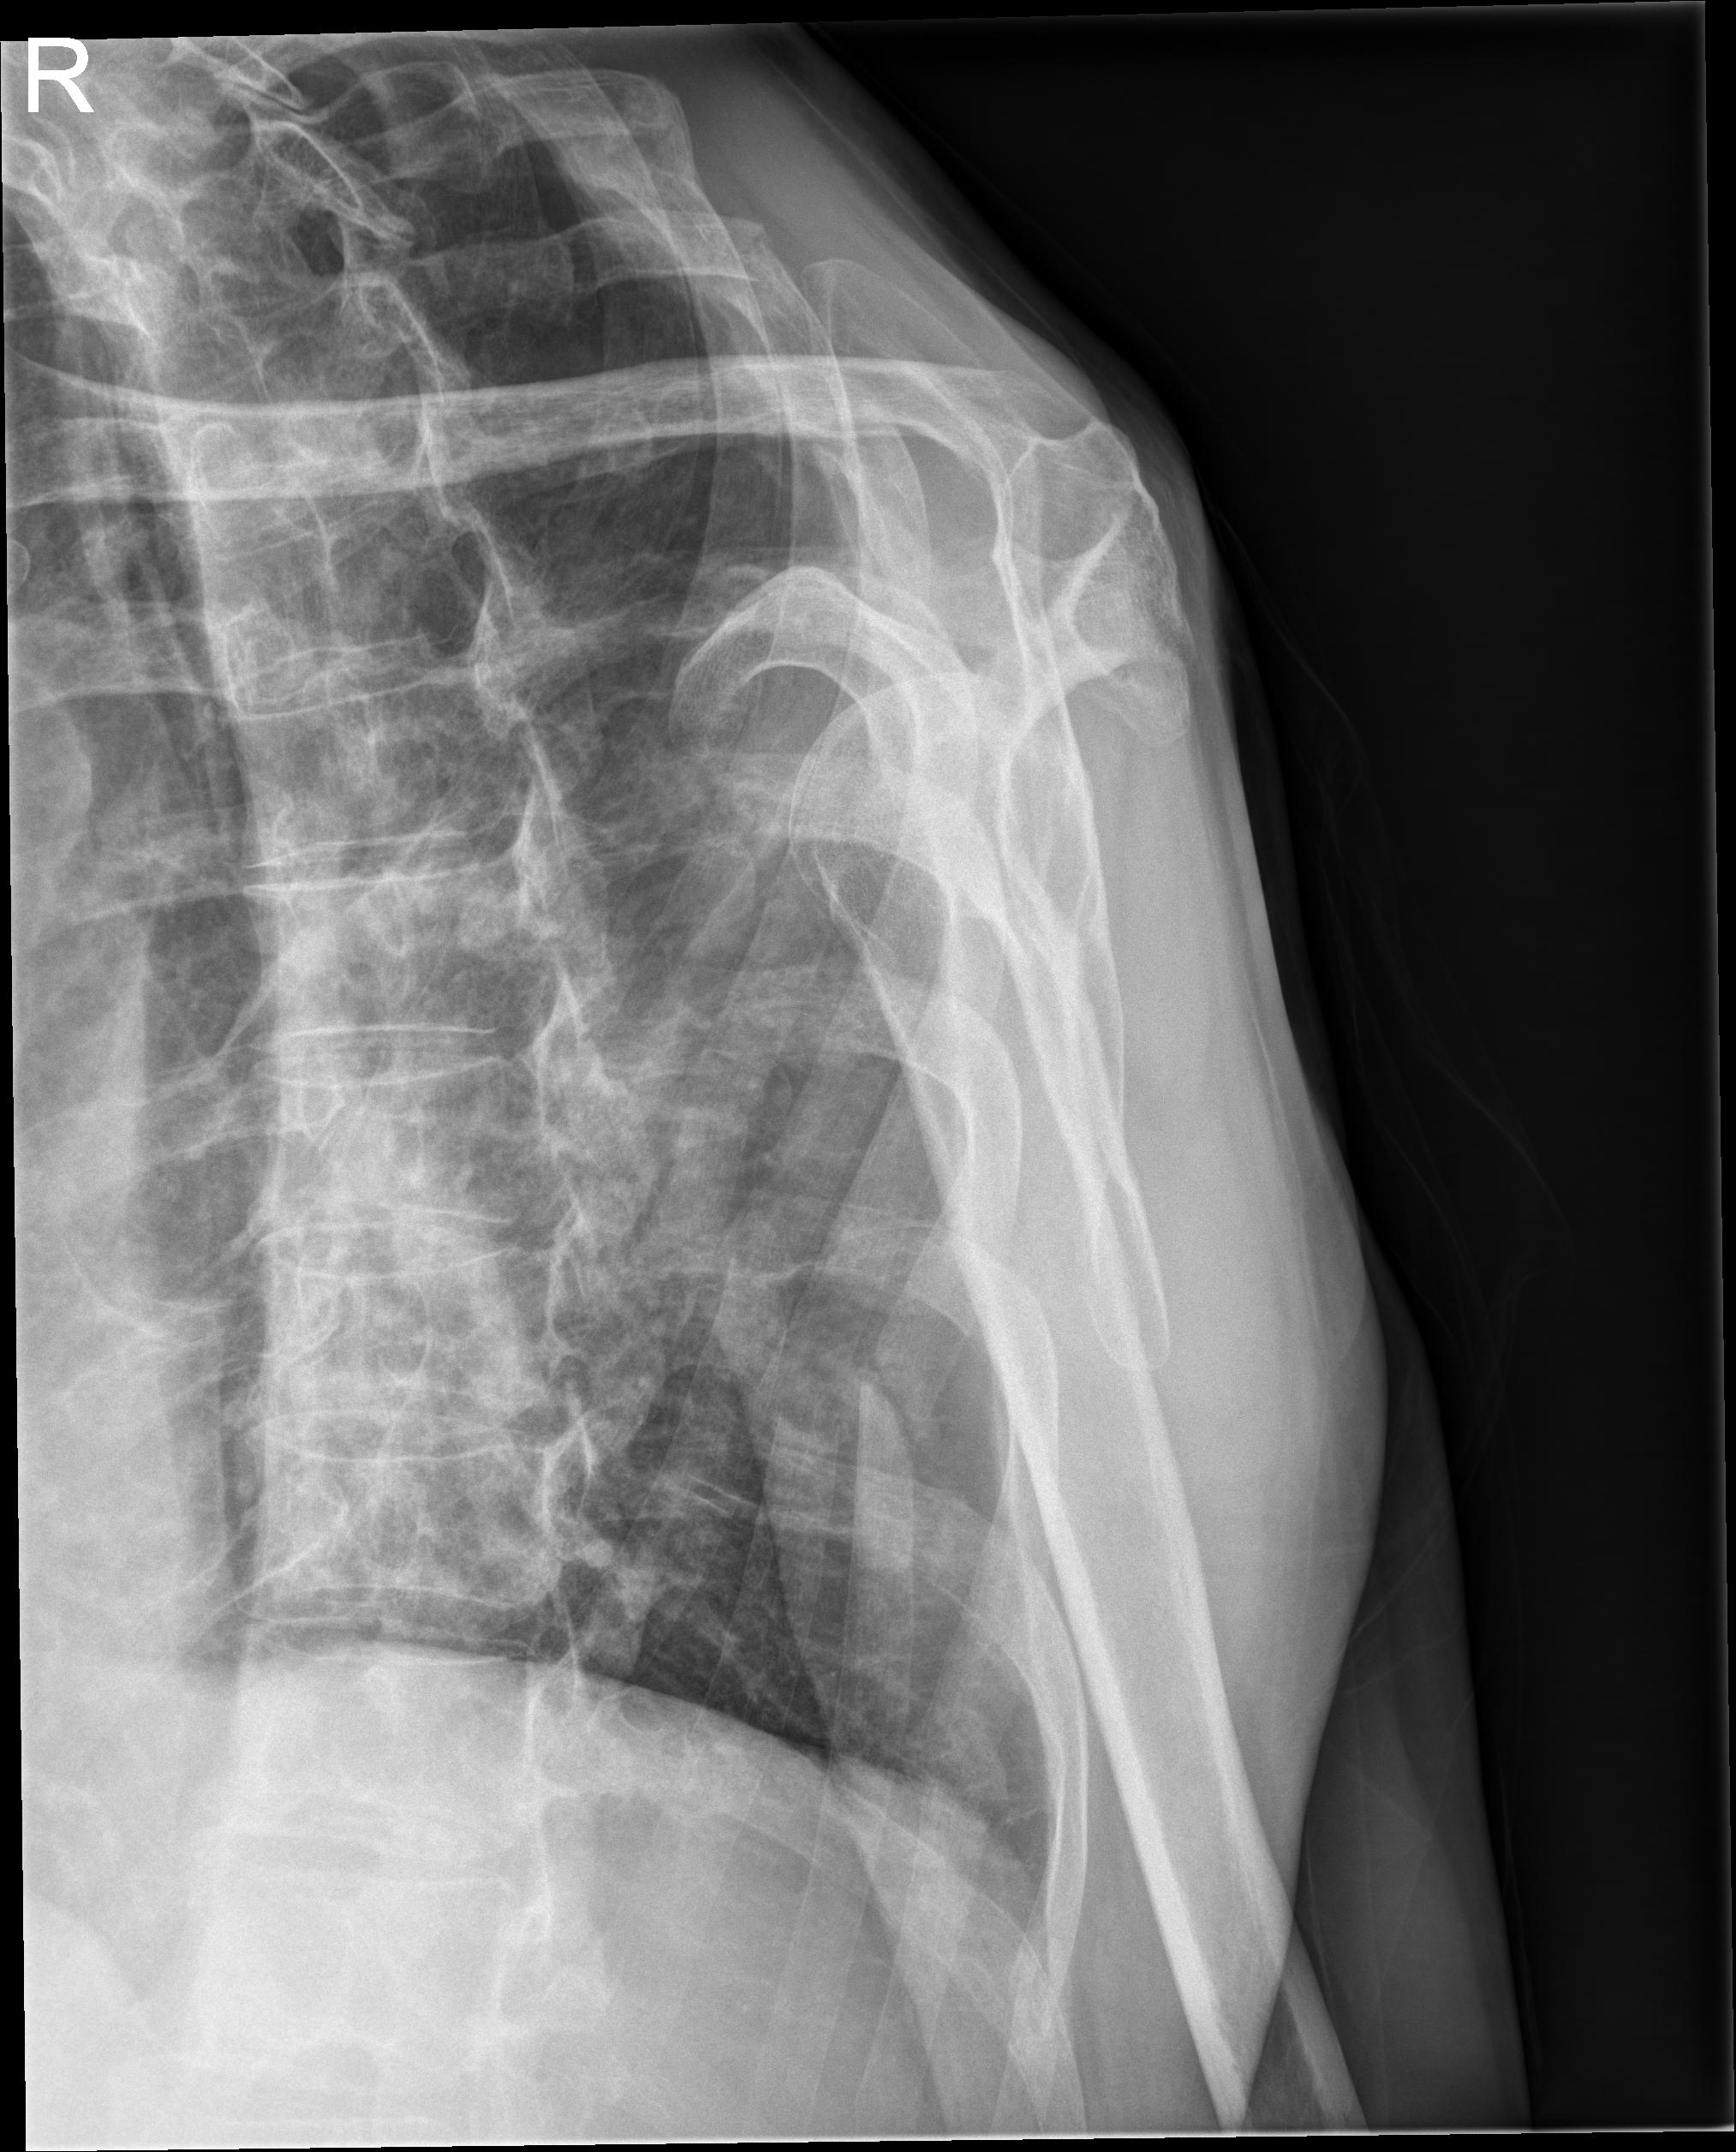

1 Hombro der.